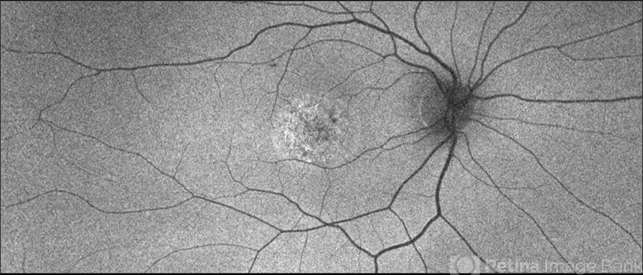

- Unilateral Acute Idiopathic Maculopathy (UAIM)

- unilateral acute idiopathic maculopathy

Scanning laser ophthalmoscope

Optos - California - Description

- 20-year-old white, male presented for initial evaluation with one week history of acute, sudden, painless loss of central vision in his right eye a week prior to presentation. - H/O short course of exogenous testosterone, Tamoxifen and Clomiphene intake ~ 2-3 weeks cycle, which was already stopped, prior to development of patient's symptoms. - H/O acute illness with generalized fatigue, malaise, URTI like symptoms and rash over the hands and chest, just prior to symptoms development, and upon further discussion, pt mentioned that few of his friends got sick around the same time. - Patient was seen the week prior by general ophthalmologist and was found to have SRF on OCT , diagnosed w/ CSCR and referred for retina evaluation. - ROS/ PMHx: Negative, healthy aside from the short illness described above - Denied any prior vision problems, similar episodes, trauma etc - VA Dsc OD: 20/400 OS:20/20 - anterior segment exam - unremarkable - posterior segment - macular RPE changes/ clumping with GA with no CME/ SRF or crystals OD, and unremarkable OS. - Pseudocolor & FAF photos: RPE changes/ clumps with GA and stippled autofluorescense OD, Unremarkable OS. - HD SD-OCT: thickened choroid, thickened/ hypertrophied subfoveal RPE with hyper-reflective material on the apical side of the retinal pigment epithelium/apical debris, subfoveal ellipsoid zone atrophy with intact ELM with no CME or SRF OD, unremarkable OS. - FA: Dye not available - ICG: deferred - mf-ERG & VF - pt rescheduled!